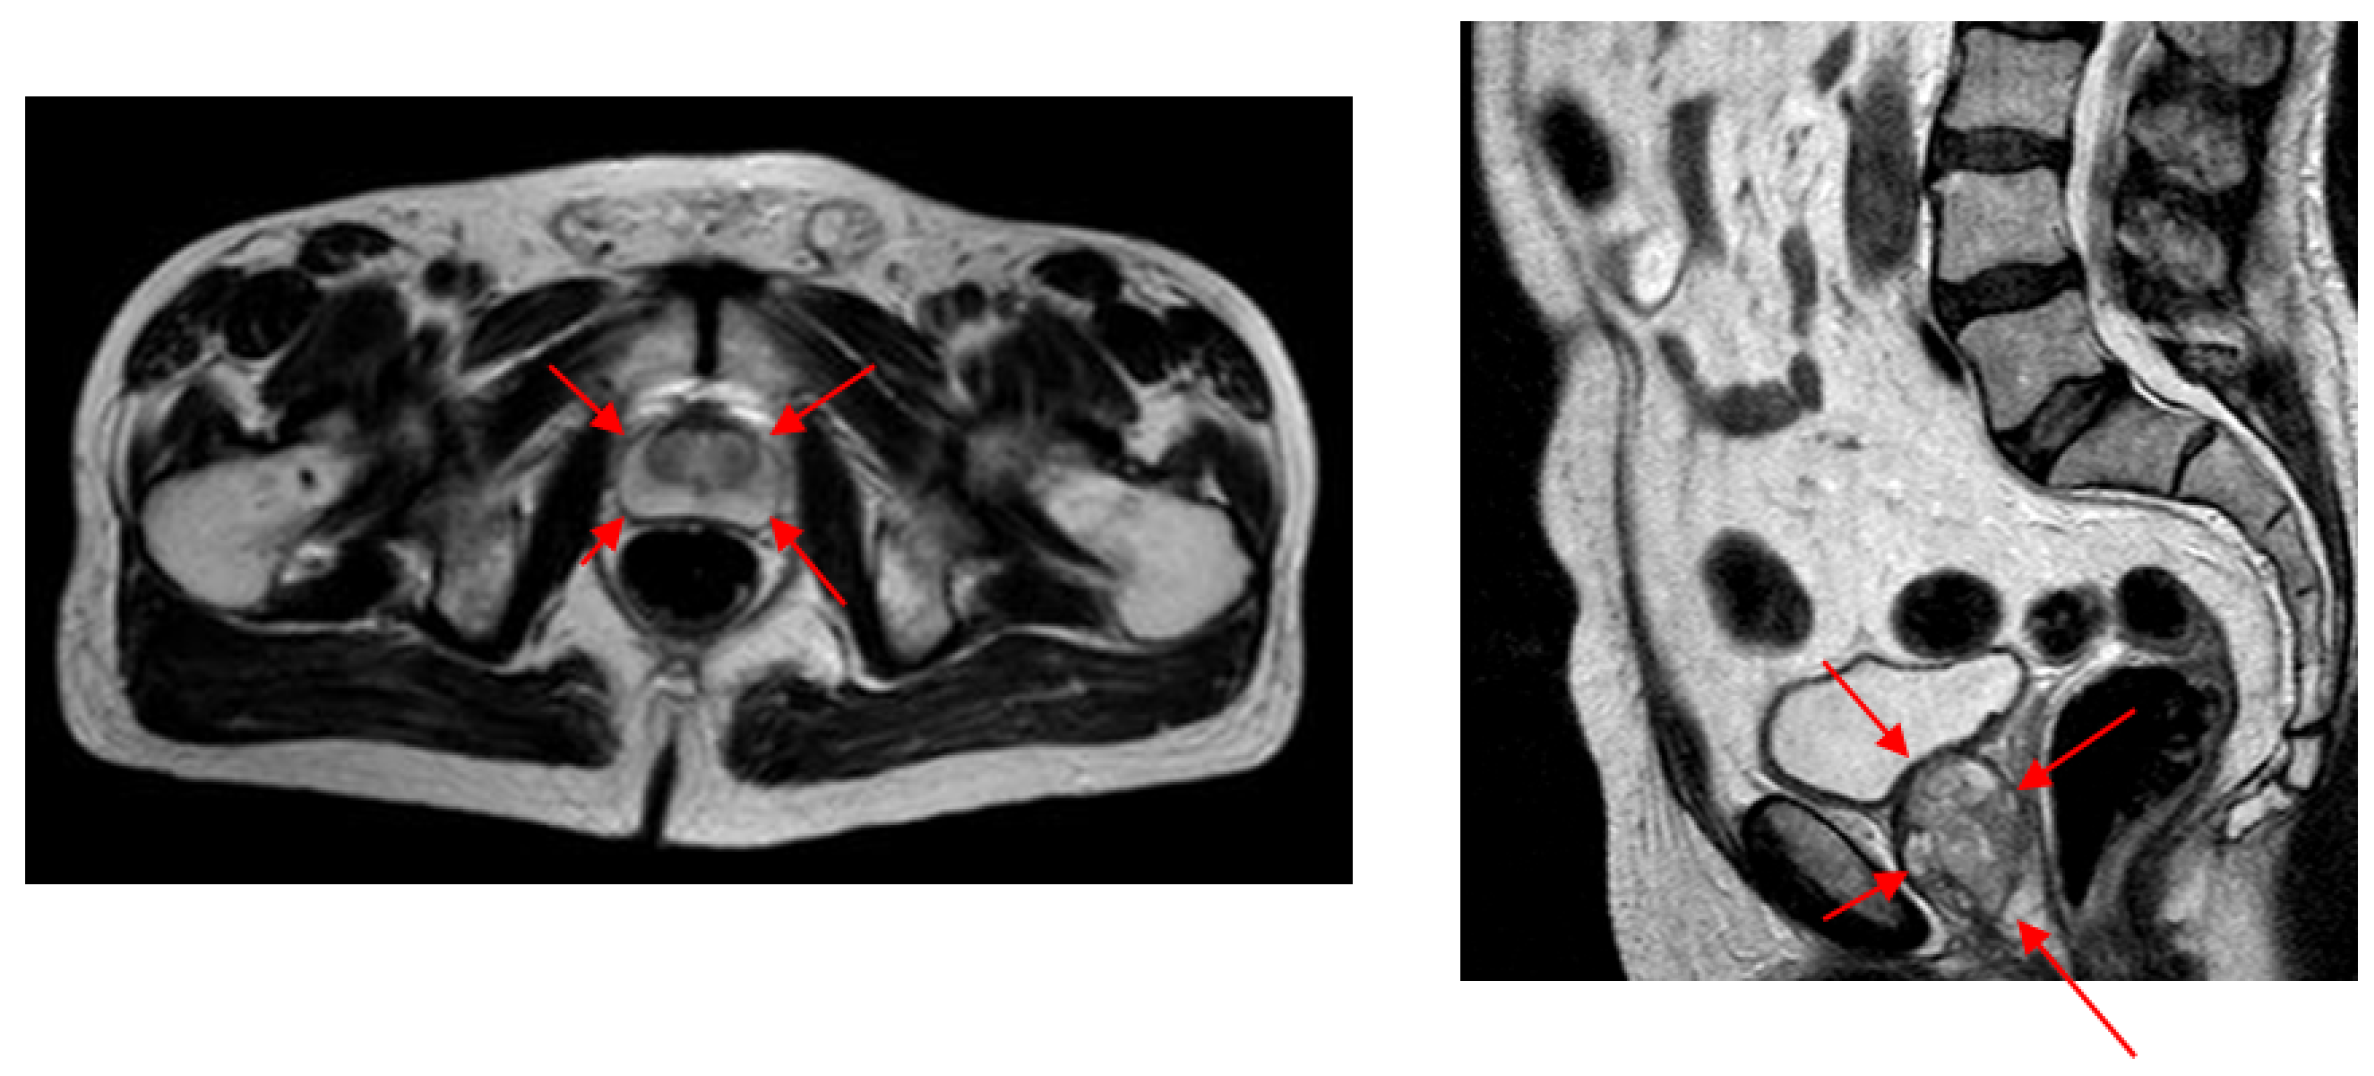

Each quadruplet patch votes for each of the ellipsoid diameter endpoints at the voting space that has the same resolution as the input image. Each quadruplet patch goes through Q D C N N T or Q D C N N S classifier networks (depending on whether it is extracted from a transverse or sagittal image) to produce c d and c o values. The actual voting happens along a circular arc where the arc center is the patch center. The arc radius is given by c d and the arc center angle by c o . The arc thickness and length are determined by the median and range of the distance and orientation class intervals. This way, a voting map for each diameter endpoint of a given sample is created whose peak gives the location estimation of the diameter endpoint.

Figure 8 shows an example for the voting maps, arcs, and detected diameter endpoints. In Figure 8a, the arcs are drawn in red with the detected diameter endpoints in green. This sample image does not show the thickness to represent the locations of the arcs better. Figure 8b shows the detected points with red dots, while the manually annotated points are shown with green dots. Figure 8c shows the voting maps of each diameter endpoint. A Gaussian smoothing filter convolves these maps to suppress the noise in these images.

Figure 8. For a given transverse image, (a) shows the voting arcs (without thickness); (b) shows the detected points (reds are expert marked locations, while greens are the detected locations of the diameter end points); and (c) shows the voting maps for e 1 , e 2 , e 3 , and e 4 endpoints.